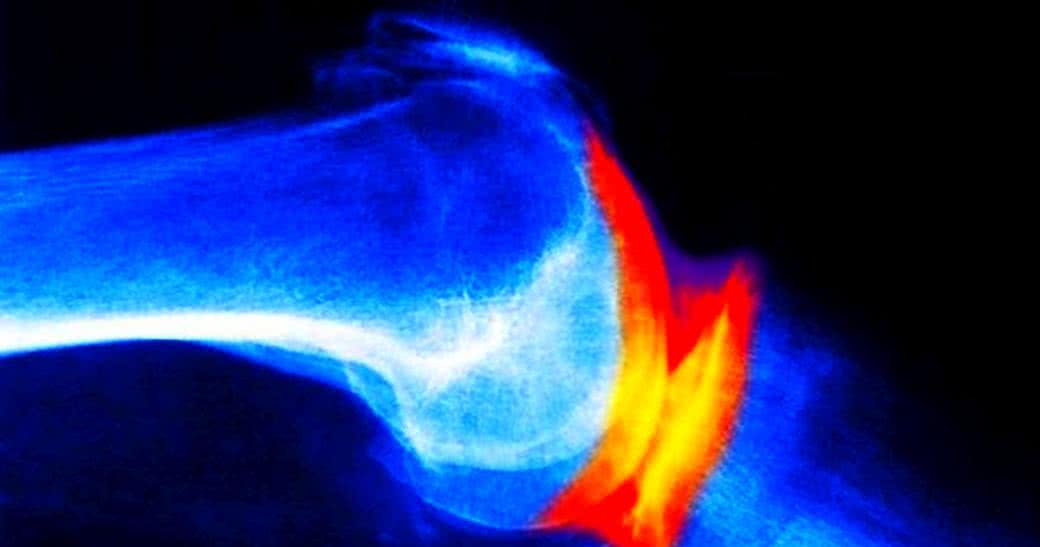

Badacze z Uniwersytetu w Montrealu po przeanalizowaniu wyników badań 194 pacjentów cierpiących na osteoartrozę stawu kolanowego, z których połowa przez dwa lata każdego dnia otrzymywała 1 200 mg chondroityny, a reszta 200 mg leku przeciwzapalnego Celebrex (celekoksib) doszli do wniosku, że wśród osób stosujących chondroitynę już po jednym roku na rezonansie magnetycznym można było zauważyć wyraźną różnicę w odczuwaniu bólu związanego z postępującą utratą chrząstki stawowej.

Choć wszyscy uczestnicy wskazywali na to, że doszło u nich do redukcji stanu zapalnego błony maziowej i obrzęku stawu, to jednak tylko w przypadku pacjentów leczonych za pomocą chondroityny obrazy rezonansu magnetycznego pokazywały zdecydowanie niższy poziom odczuwanego przez nich bólu.